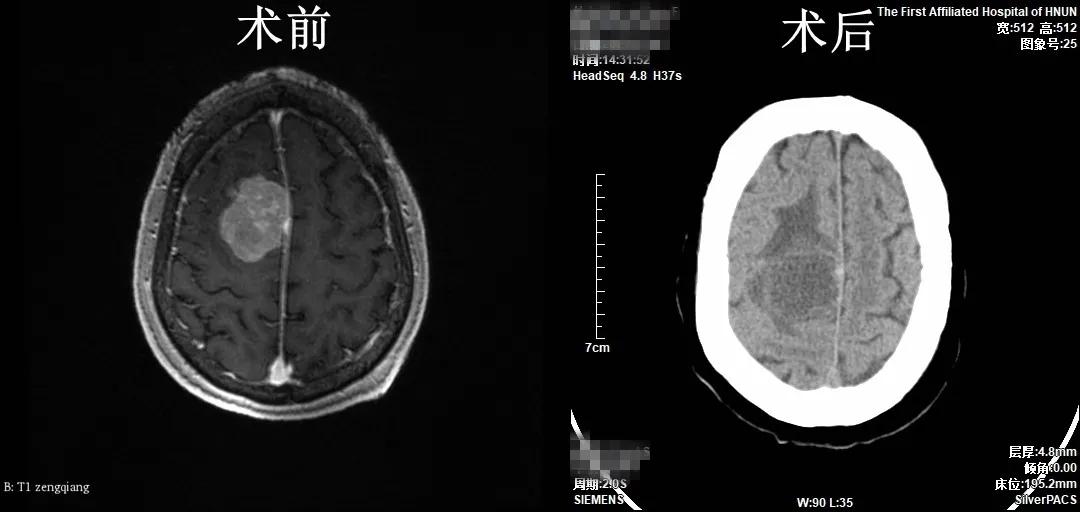

神经外科完成一例高龄患者颅内脑膜瘤切除术

患者武奶奶,82岁,近日出现头痛,间断发作,休息后可缓解,至当地医院行颅脑MRI发现“右侧额叶占位性病变”,为求手术治疗,来我院神经外科就诊。副主任医师张小广接诊患者后,行颅脑增强MRI检查回示“肿瘤位于右侧额叶,大小约42mm×36mm×32mm,与上矢状窦粘连紧密”,手术指征明确,告知家属病情,家属及患者手术愿望强烈。汇报科室副主任马建功,考虑到患者高龄,请麻醉与围术期医学科等相关科室会诊,评估患者手术风险,主治医师王晓斌运用3D-slicer及Sina软件重建患者肿瘤与血管关系三维模型、精确定位肿瘤部位。经充分术前准备及讨论,主任医师方树民带领张小广为患者实施了“显微镜下右额顶开颅矢状窦旁脑膜瘤切除术+颅骨成形术”,手术历时近5小时,手术顺利,完整切除肿瘤。术后病理结果为脑膜瘤。患者恢复顺利,无明显神经功能障碍,痊愈出院。患者及家属对我院神经外科的高超技术及优质服务赞不绝口。

(神经外科 王晓斌)